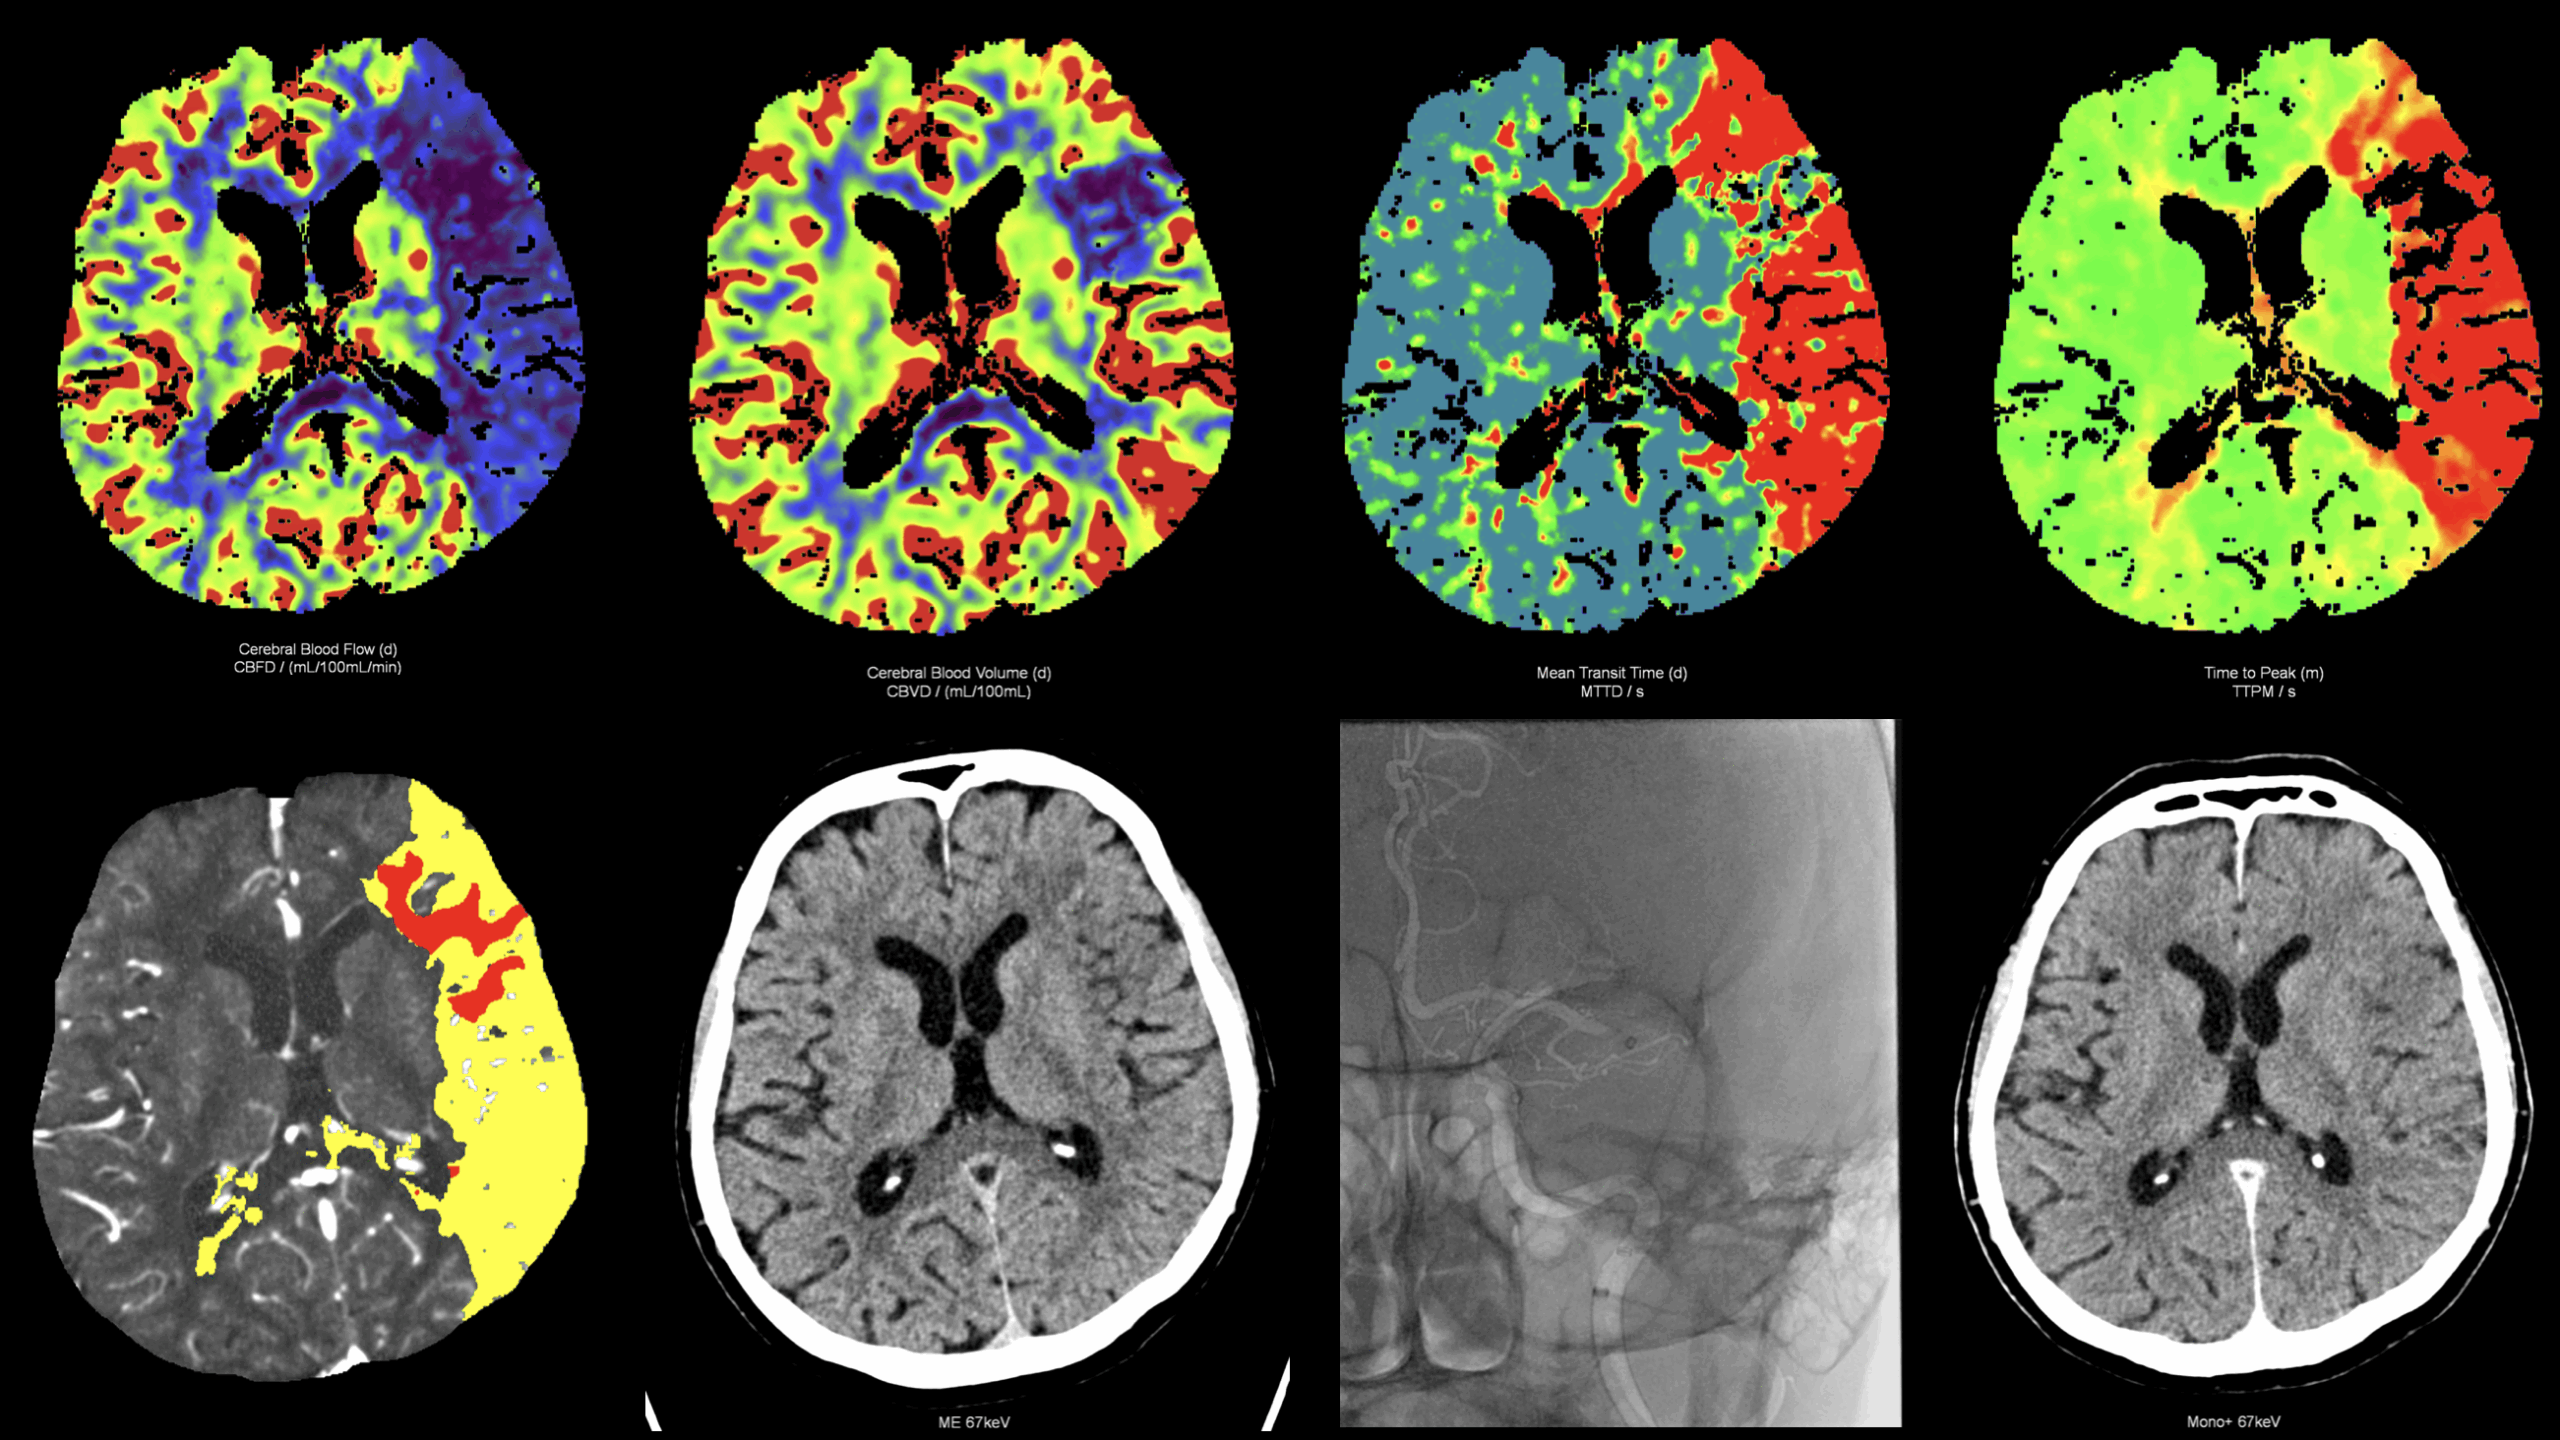

na pracovištích Kliniky zobrazovacích metod provádíme diagnostiku a také léčbu mozkové ischémie – mozkové mrtvice. Protože její výsledek je závislý na včasném zahájení léčby, přivolejte pomoc okamžitě osobě, která náhle přestala mluvit, nebo hýbat pravou nebo levou polovinou těla. Na urgentním příjmu FN Plzeň provedeme vyšetření výpočetní tomografií pomocí výpočetní tomografie, vyloučíme, že nejde o krvácení, posoudíme životaschopnost mozkové tkáně perfidním vyšetřením a zobrazíme cévy zásobující mozek CT angiografií. Následně za asistence anesteziologů provedeme zavedení speciálního nástroje do tepenného řečiště přes stehenní tepnu. Nástroj zavedeme až do mozkové cévy, ze které odstraníme krvení sraženinu a obnovíme průtok do postižené oblasti mozku. Čím dříve se tok krve obnoví tím méně odumře nervových buněk mozku – neuronů a tím je menší výsledné postižení mozkových funkcí. PAMATUJTE ČAS JE MOZEK